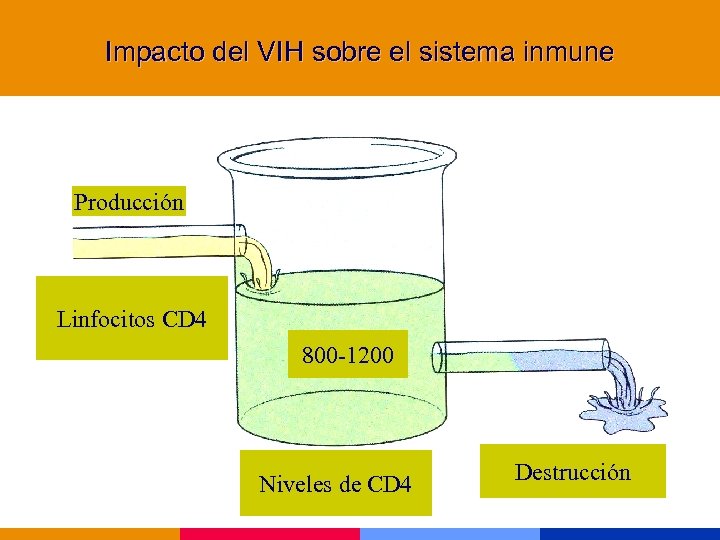

Impacto del VIH sobre el sistema inmune Producción Linfocitos CD 4 800 -1200 Niveles de CD 4 Destrucción

Impacto del VIH sobre el sistema inmune Producción Linfocitos CD 4 800 -1200 Niveles de CD 4 Destrucción